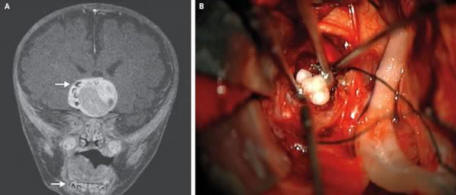

Il bambino di 4 mesi del Maryland potrebbe essere il primo una persona che aveva un tumore nel cervello che si è rivelato essere un dente. Per la prima volta i dottori sospettavano che qualcosa non andasse quando la testa del bambino sembrava cominciò a crescere più velocemente di quanto sia caratteristico dei bambini della sua età.

Una scansione del cervello ha rivelato un tumore che conteneva strutture che ricordano molto i denti umani, di solito trovate nella mascella inferiore. Il tumore è stato rimosso e ora il ragazzo si sente te stesso bene.